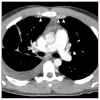

Results: The most common chest CT findings in this case series were pleural effusions and internal mammary and cardiophrenic lymphadenopathy. Pulmonary parenchymal findings included peripheral lung nodules of 1-3.5 cm in size with surrounding ground-glass opacity; many nodules had a linear track to the pleural surface that may correspond to the worm's burrow tunnel. Pericardial involvement (5/8 patients) and omental inflammation (5/7 patients), which are uncommon in Asian paragonimiasis, were common in this series.

Conclusion: Pleural and pulmonary features of North American paragonimiasis are generally similar to those reported from Asia. The presence of a track between a pulmonary nodule and the pleura may help distinguish paragonimiasis from mimickers, including chronic eosinophilic pneumonia, tuberculosis, fungal infection, or malignancy. Pericarditis, lymphadenopathy, and omental inflammation were more common in our series than in reports on paragonimiasis from other regions. These differences may be related to the infecting parasite species or to the fact that radiologic examinations in the present series were performed relatively early in the course of infection.